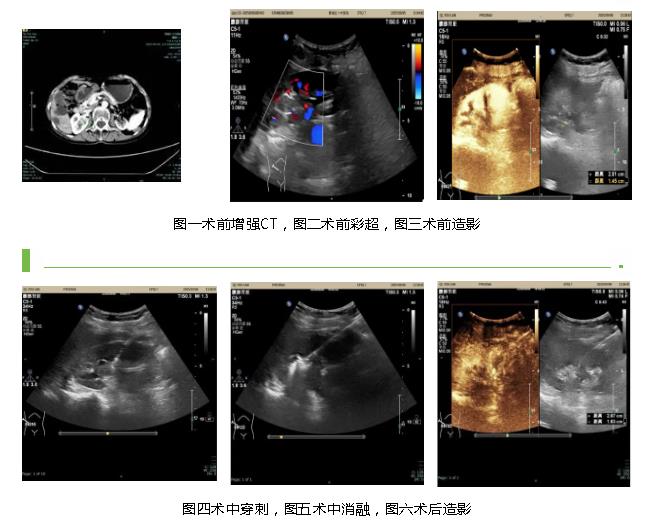

图四术中穿刺,图五术中消融,图六术后造影